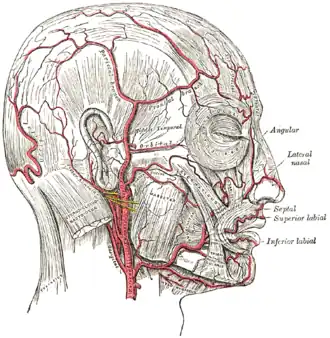

Na anatomia humana, a artéria temporal superficial é uma das artérias principais da cabeça. Surge da artéria carótida externa e bifurca na artéria temporal superficial e na artéria maxilar.

Começa na substância da glândula parótida, atrás do pescoço e da mandíbula, e cruza em cima da raiz posterior do processo zigomático do osso temporal; aproximadamente 5 cm. sobre este processo divide em dois ramos, um frontal e um parietal.

Como cruza o processo zigomático, está coberta pelo músculo anterior auricular, e por um fascia denso; é cruzada pelo ramo temporal e zigomático do nervo facial e uma ou duas veias, e é acompanhado pelo nervo aurículo-temporal que fica atrás disto.

A artéria temporal superficial faz anastomose com a artéria supra-orbital da artéria carótida interna (entre outras).

Visão frontal dos vasos sanguíneos dos próximos às sobrancelhas.

Visão frontal dos vasos sanguíneos dos próximos às sobrancelhas.